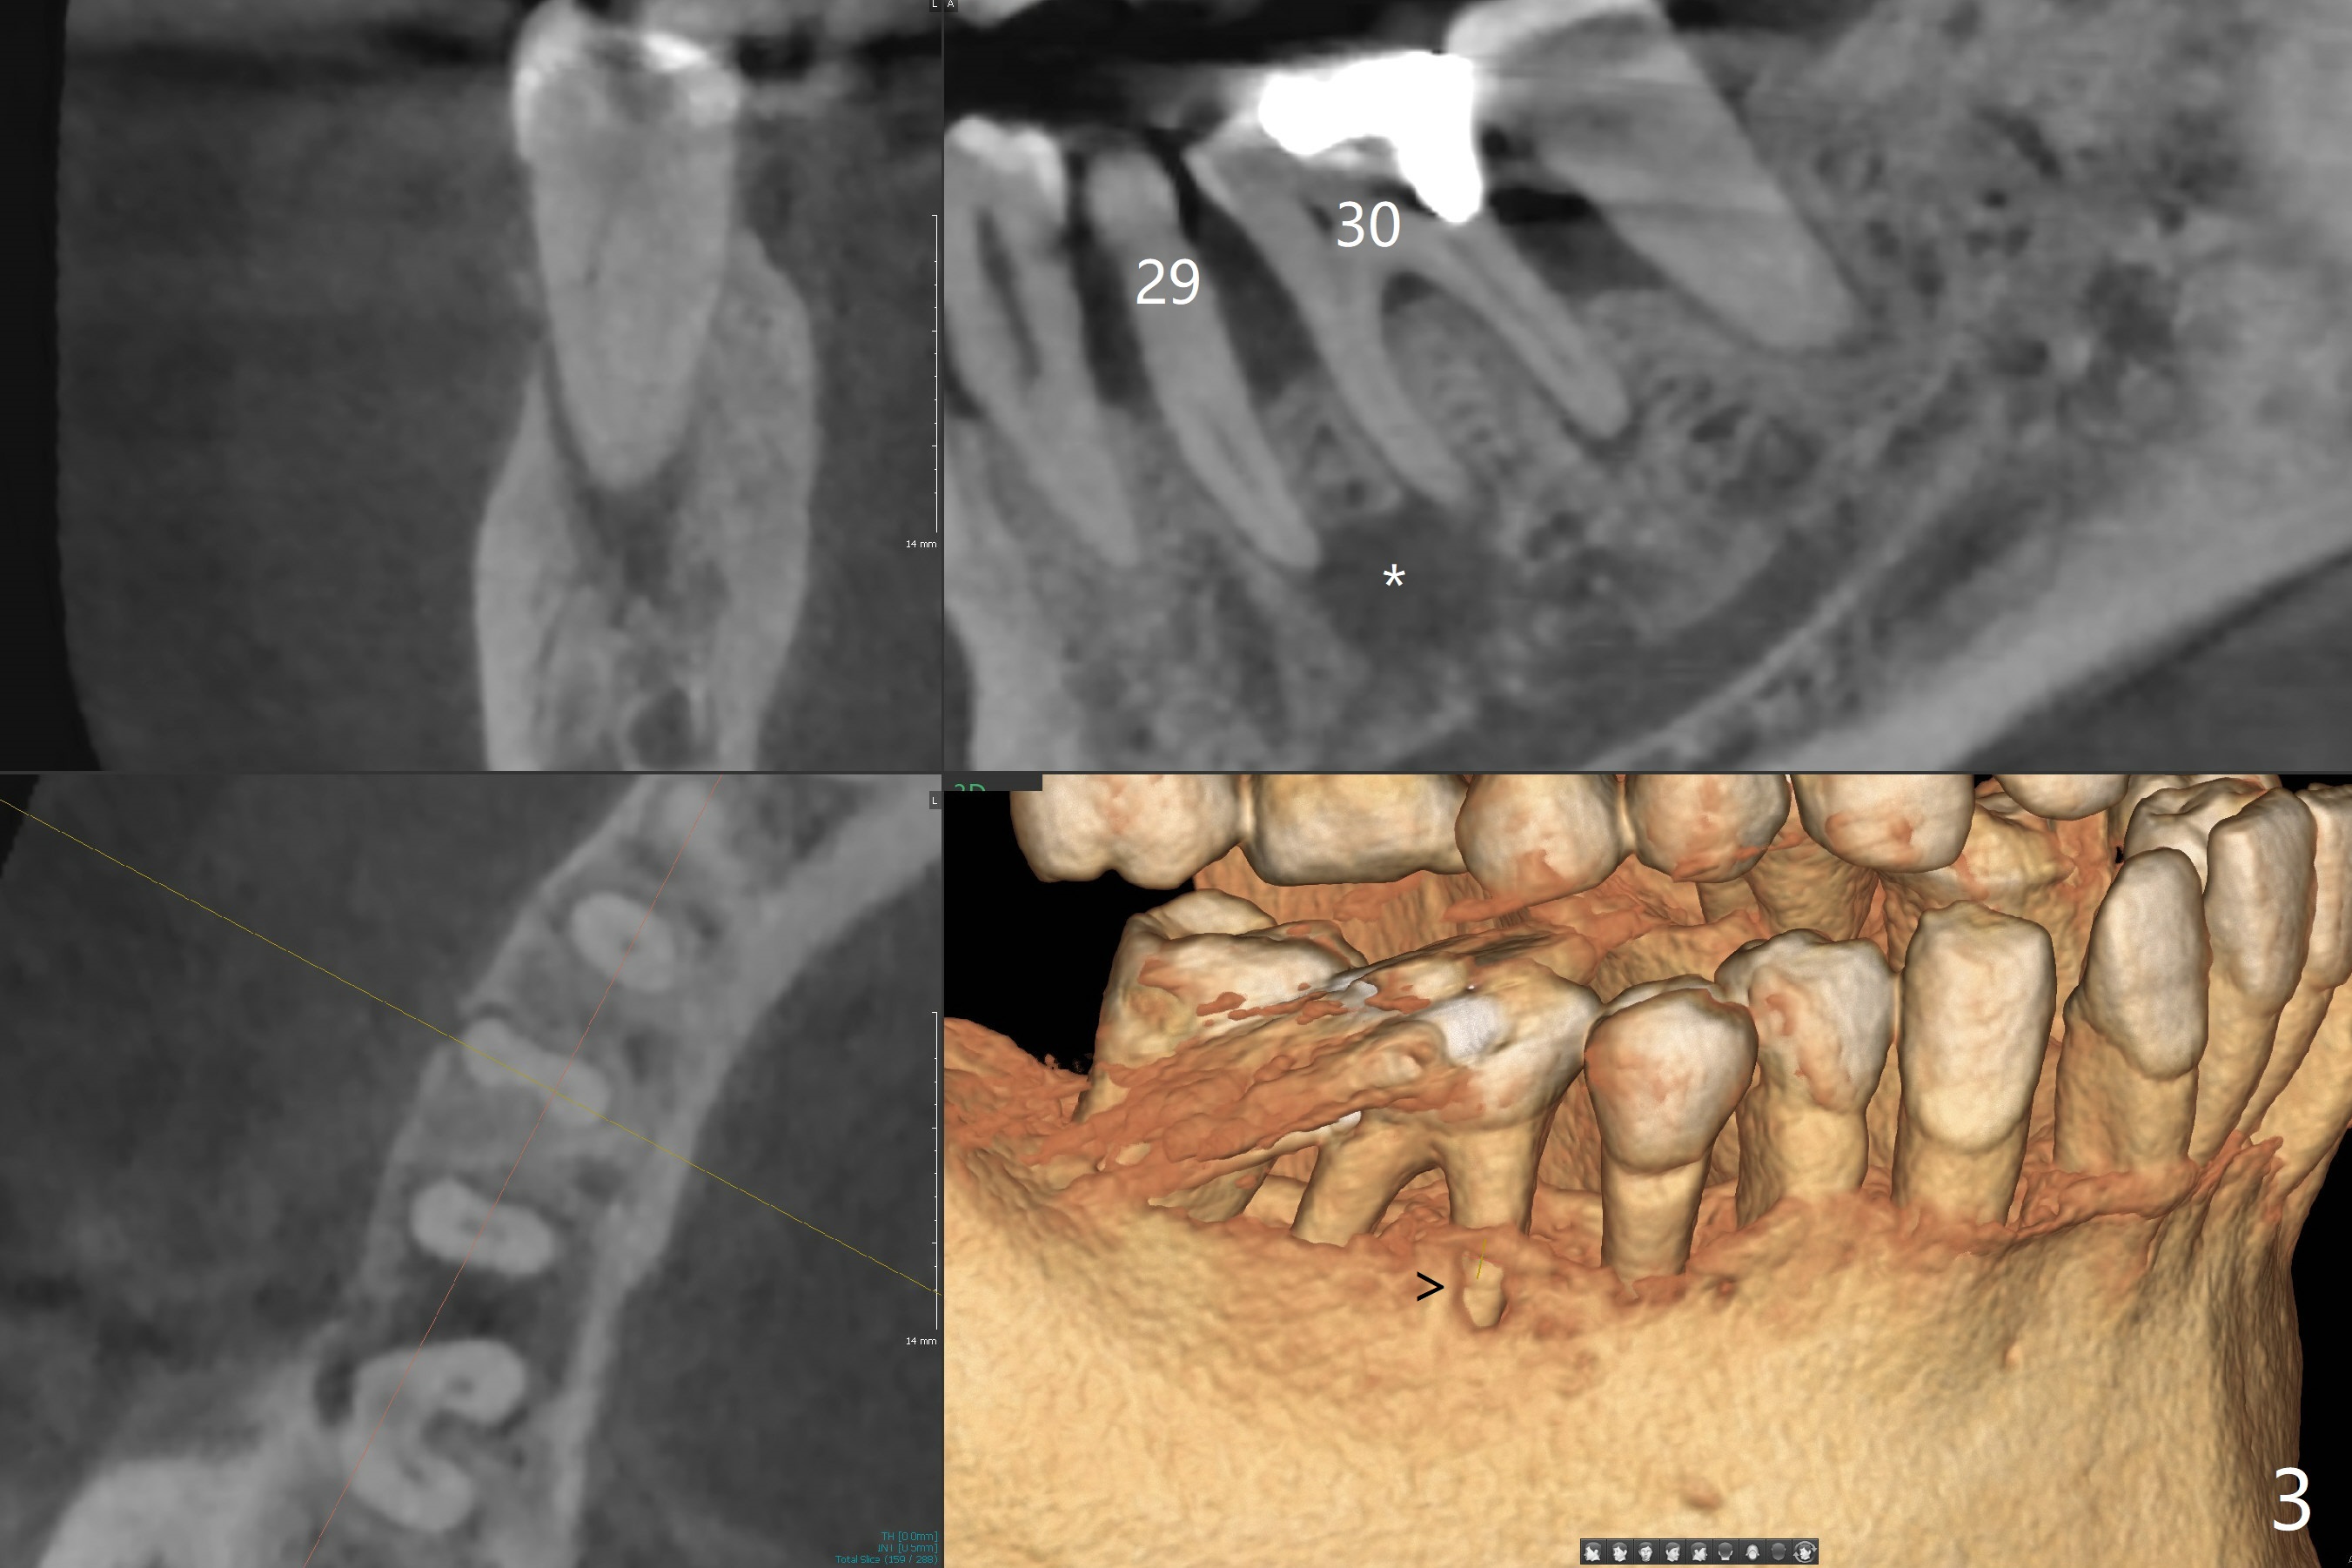

A 60-year-old man (smoker, 1/3 to 1/2 ppd) with large DO amalgam at #30 develops pain and mild swelling apparently apical to #29 (Fig.1-3). Both teeth (having fused PARL (periapical radiolucency) *) have mild percussion with the tooth #29 having higher mobility. CBCT shows apical defect (Fig.3 >). Three weeks earlier, the tooth #19 had much more severe infection with a similar apical defect (Fig.4 >). Combined with history of repeated infection associated with #30, the tooth is extracted with difficulty in obtain sound anesthesia. Socket preservation is performed instead of immediate implant (Fig.5 (*: Vanilla Graft)). CBCT makes it easy to diagnose 2 canals at #28 (Fig.6 as compared to Fig.2). Pain gradually decreases 3 days postop. In fact he has hypertension and smokes.